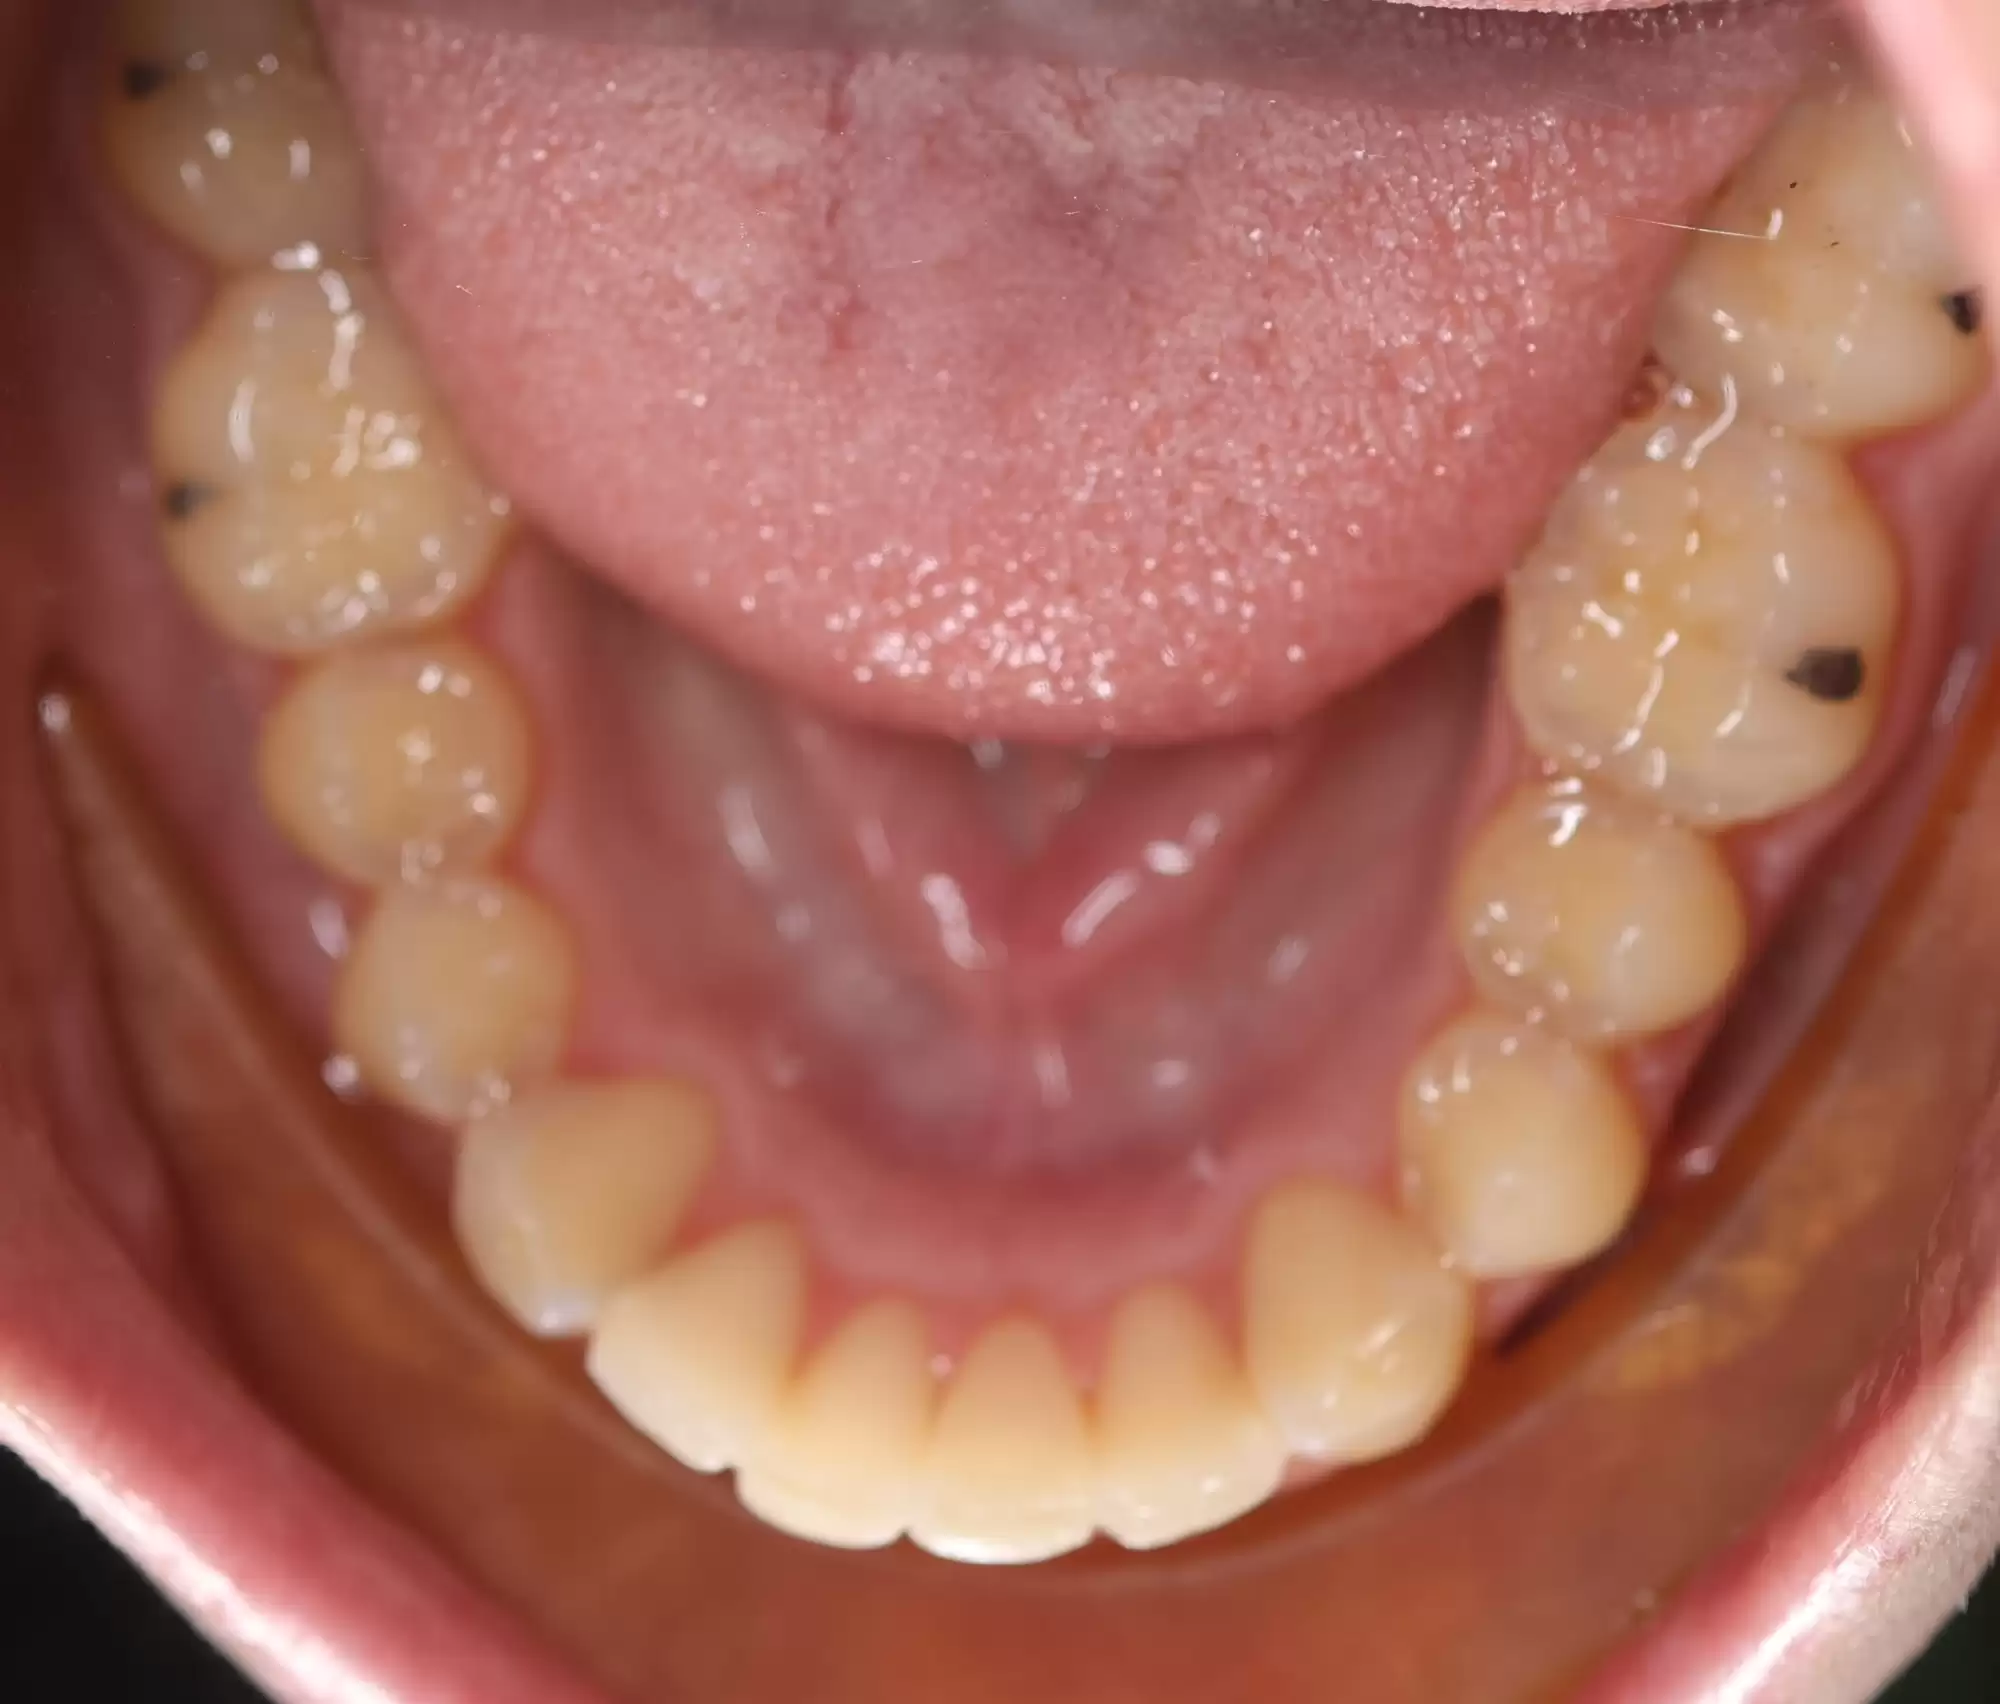

This patient had lower anterior crowding that was corrected to a well-aligned lower arch.